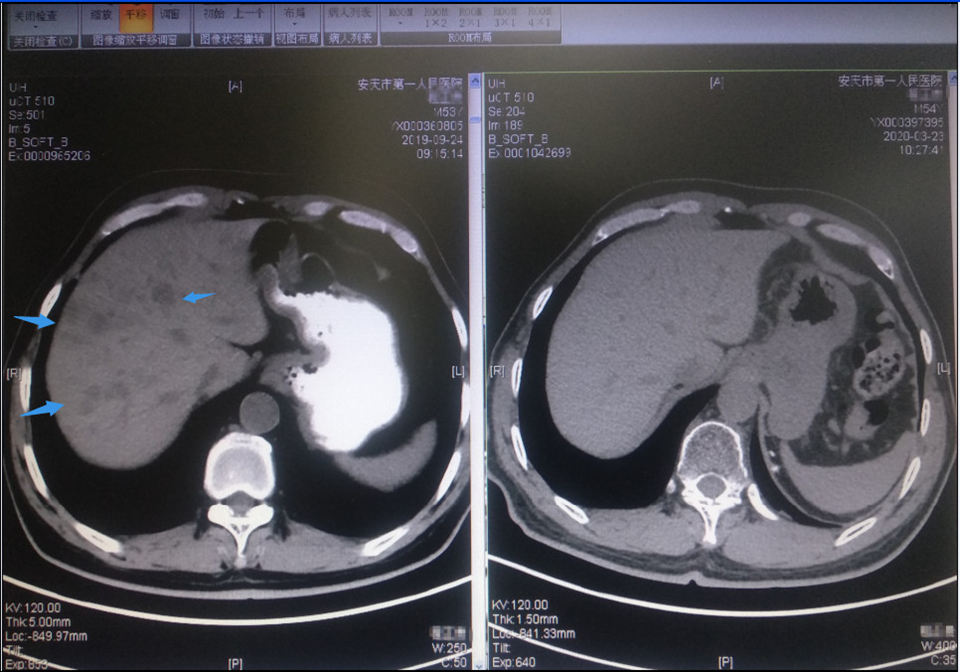

患者程XX,男,54岁。2018年11月,因“渐进性左侧腰痛加重2月”就诊,CT提示左侧腹膜后、左侧肾实质及肾门多发占位。住院行“左肾根治性切除+淋巴结清扫术”,术后病理:肾脏小细胞神经内分泌癌,肿块直径为9cm,癌组织侵犯肾盂、肾窦及肾周脂肪组织,脉管、神经见癌组织侵犯。肾门周围融合性淋巴结见癌转移,腹主动脉旁纤维组织癌浸润。术后一月就诊于我科,发现已出现锁骨上淋巴结转移。在给予三周期EP方案化疗后,肿瘤退缩不明显,并于2019年4月出现颅骨转移。我科给以颅骨局部放疗同时更换二线化疗方案为“替莫唑胺+卡培他滨”,颅骨局部转移灶控制,但仅仅过了两月(2019年6月),又出现原左肾手术区肿瘤复发,腹膜后多发淋巴结转移和多发椎骨转移。此时患者状况已经相对较差,对于二线化疗失败后的神经内分泌癌,国际上也没有肯定的治疗方案,国内仅少数文献报道抗血管生成靶向治疗可能有效,且有效率很低。为减轻患者局部复发病灶局部症状,我科再次针对于腹腔内复发病灶和骨转移灶姑息放疗并同时试用阿帕替尼抗血管生成治疗。虽然经过放疗,复发病灶病灶得以控制,但仅过一月后,患者就又再度出现了肝转移。这似乎说明,抗血管生成治疗对控制转移也无效,系统性治疗已到了无药可用的山穷水尽地步。此时,科室对于该患者的下一步处理,进行了科内讨论。最终,在基于对此类肿瘤病理学的深入研究,神经内分泌癌表现为较多淋巴细胞浸润和PD-L1表达,提示这类肿瘤可能从PD-1单抗治疗中获益。在参考其他肿瘤免疫治疗的成功经验后,同时个体化兼顾到患者当时身体状况难以耐受化疗,2019年8月份我科制定了下一步的治疗方案,继续保留副作用较小的阿帕替尼同时联合免疫检查点抑制剂特瑞普利单抗(PD-1单抗)治疗。仅仅给予了3周期的免疫联合抗血管靶向生成治疗(后因经济条件未继续治疗),患者肿瘤病灶几乎完全缓解,并持续起效。2020年3月,患者来我科复查,身体状况恢复正常, CT提示肝脏转移瘤完全消失,其他部位转移灶也继续保持接近完全缓解状态。

(免疫联合抗血管生成靶向后:箭头示多发肝转移灶消失)